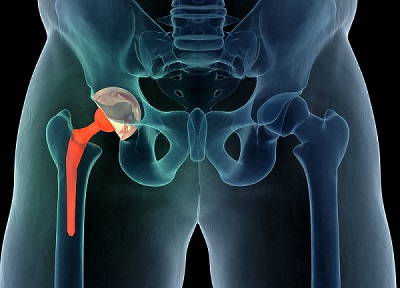

Arthroplasty is a surgical procedure designed to restore joint function. This can be achieved by resurfacing the joint's bones or by using an artificial joint (prosthesis).

MakoPlasty, also known as Robotic Assisted Joint Replacement Surgery, is a groundbreaking approach designed to benefit patients with degenerative joint conditions. Here's how it works:

MakoPlasty represents the forefront of joint replacement surgery, offering patients with degenerative joint diseases the promise of improved outcomes through state-of-the-art robotics and technology.